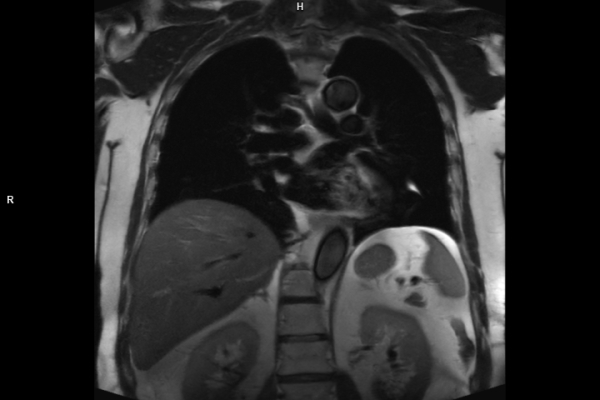

CT Untersuchung Bild

Detailbild MRT